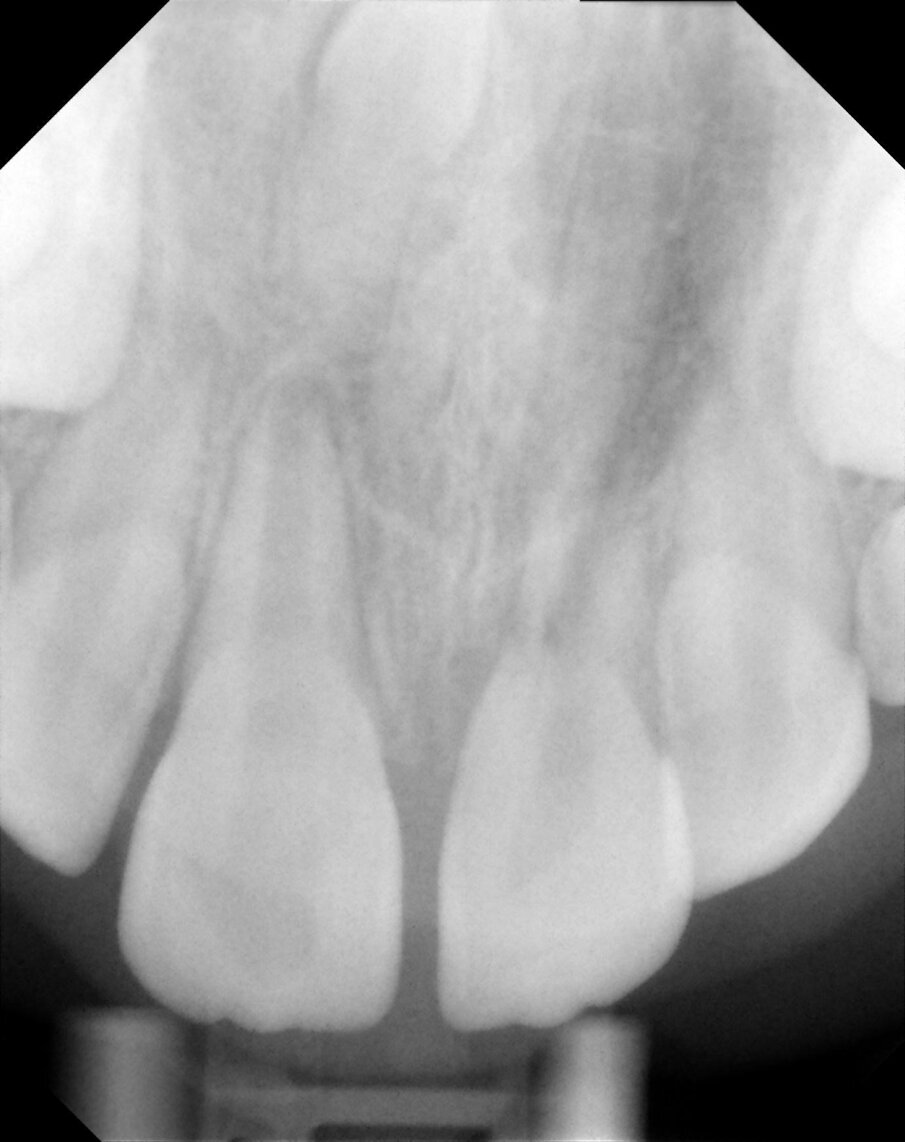

Periapical views of the upper maxillary incisors were obtained to rule out any root fractures (See Figures 4 a & b) revealed immature roots of teeth # 12, 11, 22, no root fractures and an inverted supernumerary apical to 11 and an empty socket of 21. There was no need for soft tissue radiographs as no tooth fragments were missing and the tooth was accounted for.

Figures 4a. Empty socket of 21 due to its avulsion. Notice the immature apices of 12, 11 and 22. In addition there was a supernumerary tooth/mesiodens

Figures 4b. Empy socket of 21 due to its avulsion. Notice the immature apices of 12, 11 and 22. In addition there was a supernumerary tooth/mesiodens